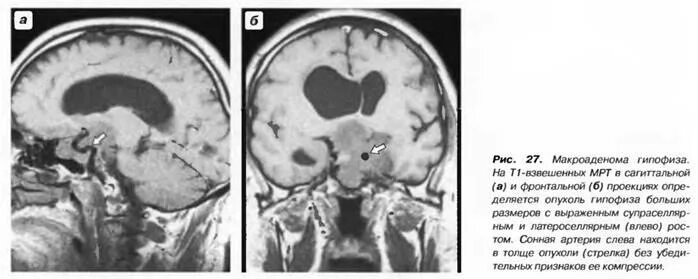

Макроаденома гипофиза